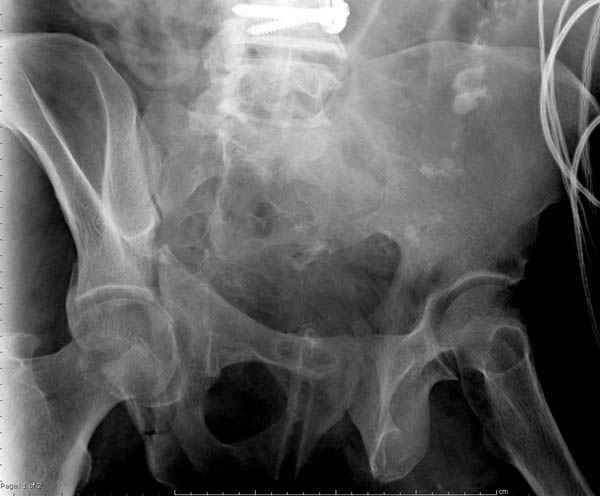

По возможности вышлите снимки, сканы таза до

реконструкции, интраоперационные.

По снимку создается впечатление о высоком поперечном переломе, задней колонны, стенки; почему не пользовались *magic screw*?

Латеральное положение облегчает проведение тракции через вертел, за 5 мм стержень за вертел (грузом через тракционное приспособление), на обычном рентгенопрозрачном операционном столе, а для положения на животе, наверное, Judet Table более приемлем, потому что там имеется латеральное тракционное устроиство.

Там множество обычных 2.7 мм шурупов, потом идет фиксация основными пластинами.

Снимки здесь....